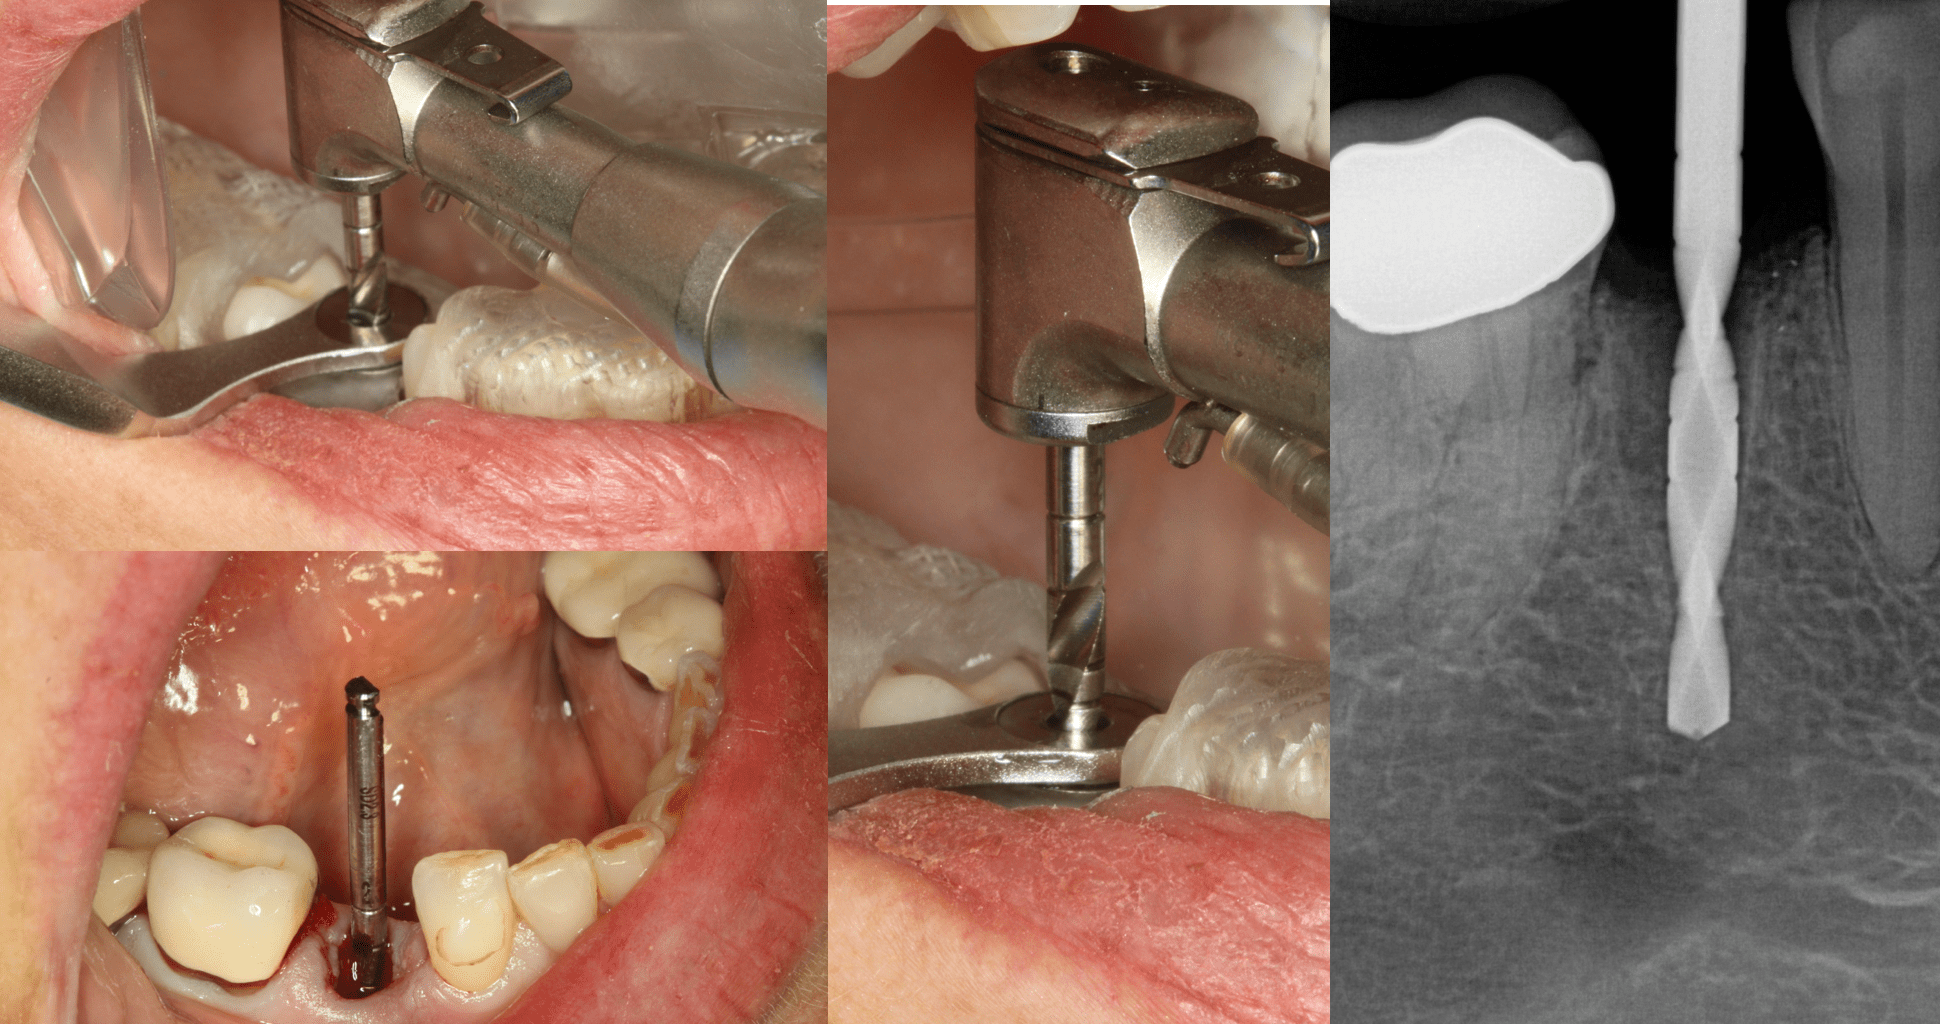

Flapless Dental Implant. When to Use a Flapless Technique? Dental Implant Osteotomy Drills This study investigates a novel approach to dental implant osteotomy, aiming to simplify the procedure by employing a single drill without the use of. Many different osteotomy procedures has been proposed in the literature for dental implant site preparation. Clinical experience shows that irrigation may not induce osseous overheating that prevents successful. When preparing and placing implants into bone tissue,. Dental Implant Osteotomy Drills.

From glidewelldental.com

Flapless Dental Implant. When to Use a Flapless Technique? Dental Implant Osteotomy Drills Measures to reduce heat generation by dental implant drills during osteotomy. Several studies have been developed with different irrigation systems and with different drill designs to improve and decrease trauma. Irrigation may not be necessary. Many different osteotomy procedures has been proposed in the literature for dental implant site preparation. This study investigates a novel approach to dental implant osteotomy,. Dental Implant Osteotomy Drills.